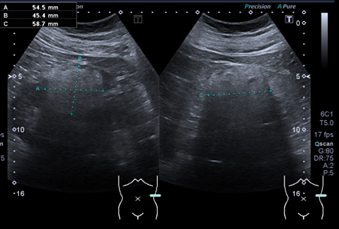

Hallazgos ecográficos

Dado el antecedente familiar de neoplasia renal, se decide realizar una ecografía abdominal en la consulta, en la cual se identifica de forma incidental una lesión cortical hiperecogénica en el riñón izquierdo, de aproximadamente 13 × 10 mm, con flujo Doppler positivo.

Ante este hallazgo, se solicita ecografía complementaria por el Servicio de Radiología, donde se confirma una lesión cortical compatible con angiomiolipoma renal izquierdo, además de observarse pequeños angiomas hepáticos sin otras alteraciones relevantes.

Tras discutir opciones terapéuticas y riesgos, se decide realizar embolización selectiva de la lesión, procedimiento que transcurre sin incidencias. En el control ecográfico realizado dos meses después, se objetiva una reducción del tamaño tumoral a 56 mm. Paralelamente, desde Urología se deriva a Nefrología para reevaluación de la HTA y ajuste terapéutico, ante la posibilidad de que el angiomiolipoma estuviera contribuyendo a la inestabilidad tensional.